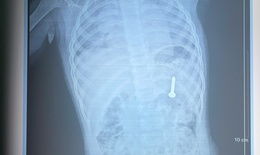

Việt kiều Mỹ 73 tuổi lựa chọn về Việt Nam phẫu thuật khối u đại tràng ác tính

Camera bệnh viện - 10/10/2025 14:55SKĐS - Việt kiều Mỹ 73 tuổi quyết định đến Bệnh viện Đa khoa Thủ Đức để thăm khám sau khi xuất hiện các dấu hiệu bất thường về đường tiêu hóa. Kết quả phát hiện khối u đại tràng ác nên nhanh chóng được phẫu thuật cắt bỏ.